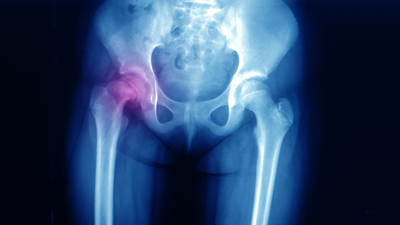

Haberler Sağlık Doğuştan Kalça Çıkığı Nedir ve Nasıl Anlaşılır? Doğuştan Kalça Çıkığı Belirtileri ve Tedavisi Nelerdir? | Sağlık Haberleri

Çocukların gelişim dönemlerinde ortaya çıkan bazı belirtiler ile tespit edilen doğuştan kalça çıkıklığı, yetişkinlik dönemlerinde yürüme problemlerinden ayakta durmaya kadar, pek çok temel hareket fonksiyonunu olumsuz etkiler. Bunun için doğuştan kalça çıkığı sorunun erken tespiti önemli yer tutar.

Doğuştan kalça çıkığı önemli bir sağlık problemidir. Bazı bebeklerde ve çocuklarda kalça eklemini oluşturan dokularda gelişme döneminde aksaklıklar meydana gelebilir. Gelişim döneminde eklemlerde meydana gelen bu aksaklıklar gelecek için ciddi eklem sorunlarına yol açar ve kişilerin yaşam kalitesini düşürür. Doğuştan kalça çıkığı problemi, her bin bebekten birinde görülebilen bir hastalıktır. Erken teşhis ve doğru tedavi hastalığın ileriki dönemde sorun yaratmaması için önem arz eder.

Doğuştan Kalça Çıkığı Nasıl Anlaşılır?

Doğuştan kalça çıkığının tedavisi için erken teşhis çok önemlidir. Bu yüzden anne ve baba adaylarının dikkatli olması ve bebeğin vücudundaki değişimleri doğru gözlemlemesi gerekmektedir. Bunun yanı sıra bebeklerde 3 ayda bir yapılan test ve taramalarda doktor kontrolü de doğuştan kalça çıkıklığının tespiti için hayati bir önem taşır.